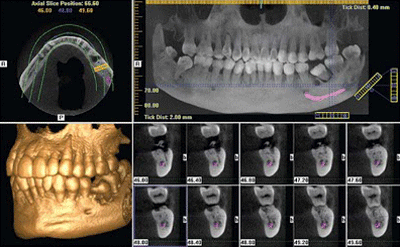

I-CAT Vision

I-CAT Vision é um software que gera imagens, onde integram módulos de visualização para ATM, implante e todos os cortes axiais, coronais e sagitais.